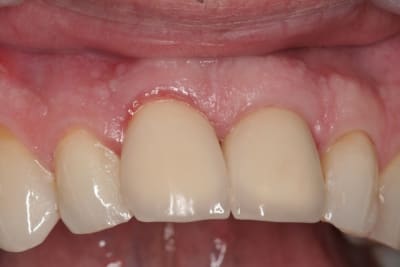

pluton

çà manque un peu de cas en ce moment...alors en voilà un ptit au passage...

11 avec résorption interne

EII avec MCI sur du dentium (4.5/14) comblement du gap vestibulaire avec du kasios tcp (très constant dans les résultats...et très économique)

la prothèse d'usage a été réalisée par ma petite associée...mais j'étais là pour superviser et faire quelques photos...;-)